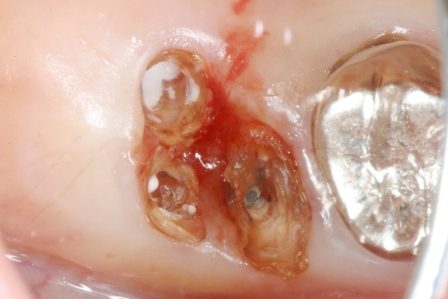

50代女性、右上7、口臭が気になる。

元々つながっていた歯根が3つに分離していて、近心根はコアがダツリしています。

メタルコアはピンで留める分割コアと、凝った作りです。

冠を外して、コアを削り取って、ピンも削り取って、虫歯も削り取って少しだけきれいにしました。

α-TCPセメントを充填してしばらく放置します。